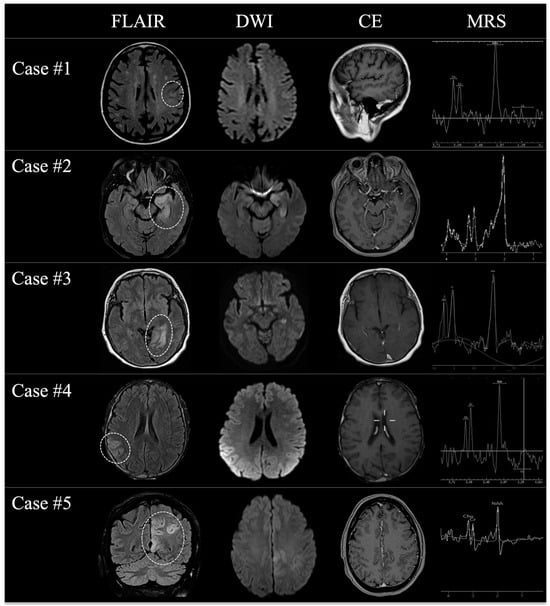

| Major MRI findings | Left parieto-occipital and thalamic FLAIR hyperintensities, with bilateral mesial temporal changes | Left mesial temporal lobe cortical thickening with FLAIR hyperintensity (subtle changes in right internal capsule) | Posterior left mesial temporal lobe FLAIR hyperintensity and ribbon-like cortical thickening | Right cortical frontal precentral FLAIR hyperintensity with no cortical thickening; subtle bilateral temporal changes (left > right) | Left cortical frontal-parietal, precentral FLAIR hyperintensity with ribbon-like thickening; subtle bilateral temporal changes (left > right) |

| CE | Absent | Absent | Absent | Absent | Absent |

| MRS | Partial Cho/Cr ratio inversion | NSTR | Moderate NAA reduction | NSTR | Partial Cho/Cr ratio inversion |

| First to second MRI scan interval (weeks) | 4 | 6 | 8 | 4 | 6 |

| Major MRI findings | Expansile edematous intra-axial lesion | Expansile edematous intra-axial lesion | Expansile edematous intra-axial lesion | Expansile edematous intra-axial lesion | Expansile edematous intra-axial lesion |

| Localization | Left parieto-occipital lobe | Left temporal lobe | Left temporal lobe | Right fronto-parietal region | Frontal lobe |

| CE | Irregular ring enhancement with inner necrotic core | Irregular ring enhancement with inner necrotic core | Irregular patchy enhancement | Irregular ring enhancement with inner necrotic core | Irregular ring enhancement with inner necrotic core |

| MRS | Increased Cho/NAA ratio, inverted Cho/Cr ratio, mild Lip-Lactate peak | Artifacts (significant NAA depletion, inverted Cho/Cr ratio) | Increased Cho/NAA ratio, inverted Cho/Cr ratio | Increased Cho/NAA ratio, inverted Cho/Cr ratio | Increased Cho/NAA ratio, inverted Cho/Cr ratio |

| Surgery | Biopsy | Gross total resection | Gross total resection | Partial resection | Partial resection |

| Pathology | GBM IDH wild-type, unmethylated | GBM IDH wild-type, unmethylated | GBM IDH wild-type, methylated | GBM IDH wild-type, unmethylated | GBM IDH wild-type, unmethylated |